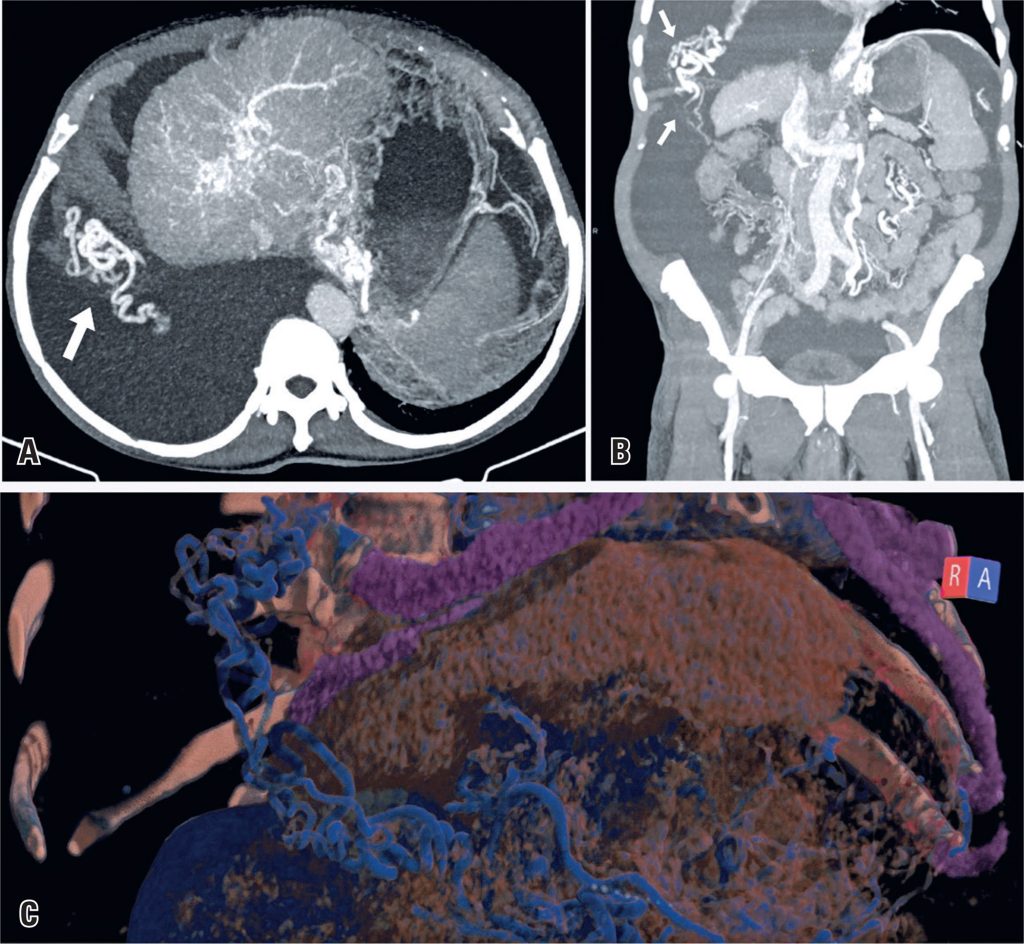

Liver cirrhosis with the development of transdiaphragmatic collateral circulation

A 70-year-old man with liver cirrhosis underwent follow-up examinations at our hospital while awaiting liver transplantation. His medical history included an episode of upper gastrointestinal bleeding secondary to the rupture of esophageal varices approximately a year ago.

His computed tomography (CT) showed signs of chronic liver disease with subacute portal vein thrombosis, cavernous transformation at the abdominal level, ascites, and right pleural effusion. Furthermore, multiple collateral vessels were observed, some of which ascended through the right hemidiaphragm to communicate with the pulmonary veins, which is consistent with transdiaphragmatic collateral circulation ().